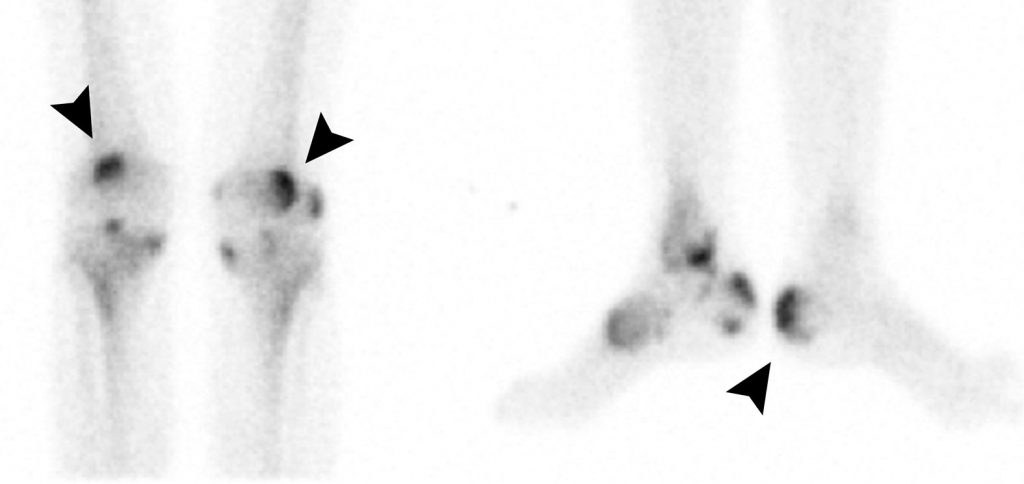

La scintigraphie osseuse permet l’exploration de l’ensemble du squelette avec mise en évidence d’hyperfixations articulaires ou des enthèses traduisant des lésions évolutives (figure 84.3).

Fig. 84.3 Spondylarthrite ankylosante.

Scintigraphie osseuse, clichés statiques tardifs centrés sur les genoux de face et les pieds de profil. Mise en évidence d’hyperfixations des genoux et des pieds en regard d’insertions tendineuses (têtes de flèche) en faveur de lésions osseuses actives de la spondylarthrite ankylosante connue.

Source : CERF, CNEBMN, 2022.